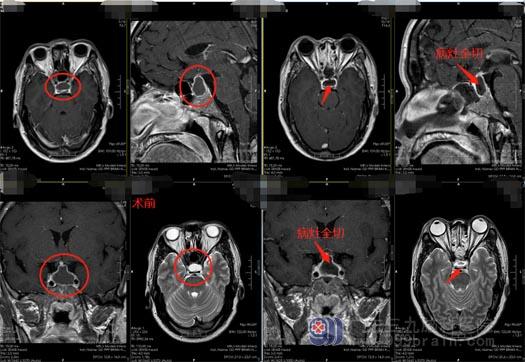

住院后通过进一步检查,柯大哥被确诊为鞍区占位,Rathke囊肿可能性大。

手术原则是彻底清除囊肿内容物,缓解囊肿对垂体组织、鞍膈、视神经、视交叉的压迫,尽量减少手术对周围垂体组织的损伤。经鼻蝶窦入路显微神经外科手术是治疗本病的首选方法,该入路创伤小、安全、术后复发率低。

由医院副院长、神经外五科主任鲁明主刀,在全麻下为柯大哥行“经鼻蝶鞍区rathke囊肿切开引流术”,手术过程顺利。术后的柯大哥没有了头痛,也无其它并发症,目前恢复得很好。